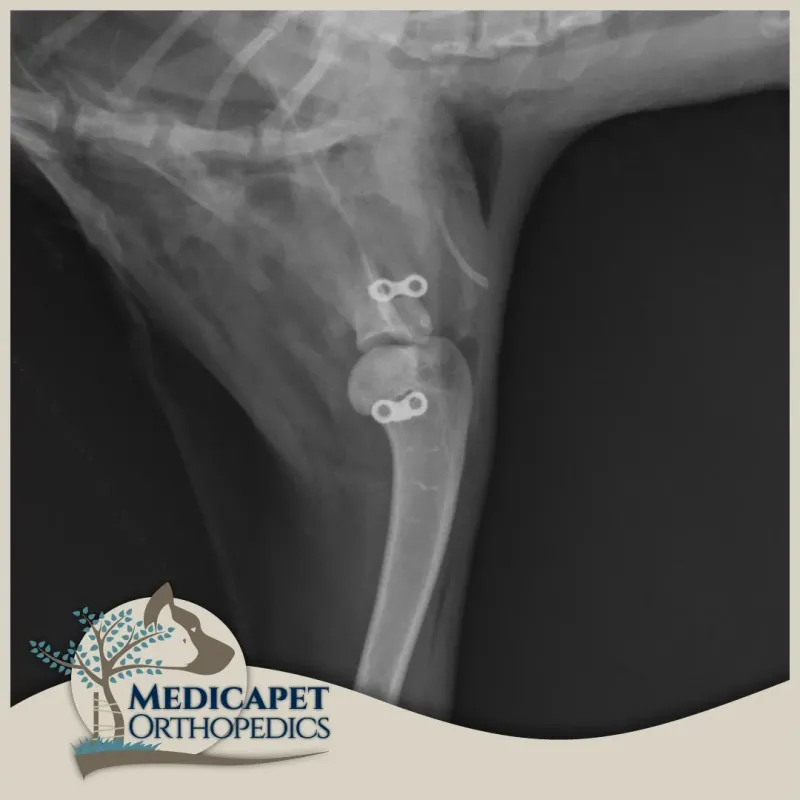

Omuz instabilitesinin tedavisi, burkulma ve zorlanma derecesine ve instabilite derecesine bağlıdır. Düşük dereceli yaralanmalar genellikle anti-inflamatuar ilaçlar, egzersiz modifikasyonu, fizyoterapi ve hidroterapi ile cerrahi olmayan bir şekilde tedavi edilir. Yüksek dereceli yaralanmalar ise stabilizasyon, omuz füzyonu veya total omuz replasmanı kullanılarak tedavi edilebilir.

omuz-instabilitesi-2